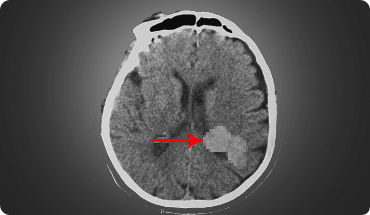

Cavernous Malformations

A cavernous malformation is a rare type of vascular condition characterised by clusters of tiny blood vessels or capillaries in the brain that is irregular and enlarged in structure.